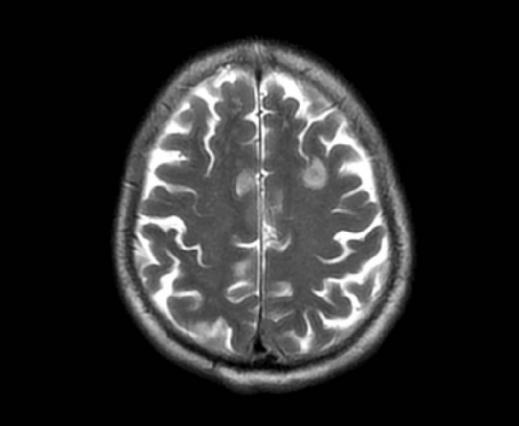

10天后,老许仍反复发热,高达39℃,甚至出现胡言乱语的症状,被当地医院转到了西湖大学医学院附属杭州市第一人民医院住院治疗。

进行了一系列检查后,医生发现老许除了肺里有个空洞结节外,大脑里还长了几个“结节”。

头颅MRI提示两侧大脑多发异常信号灶